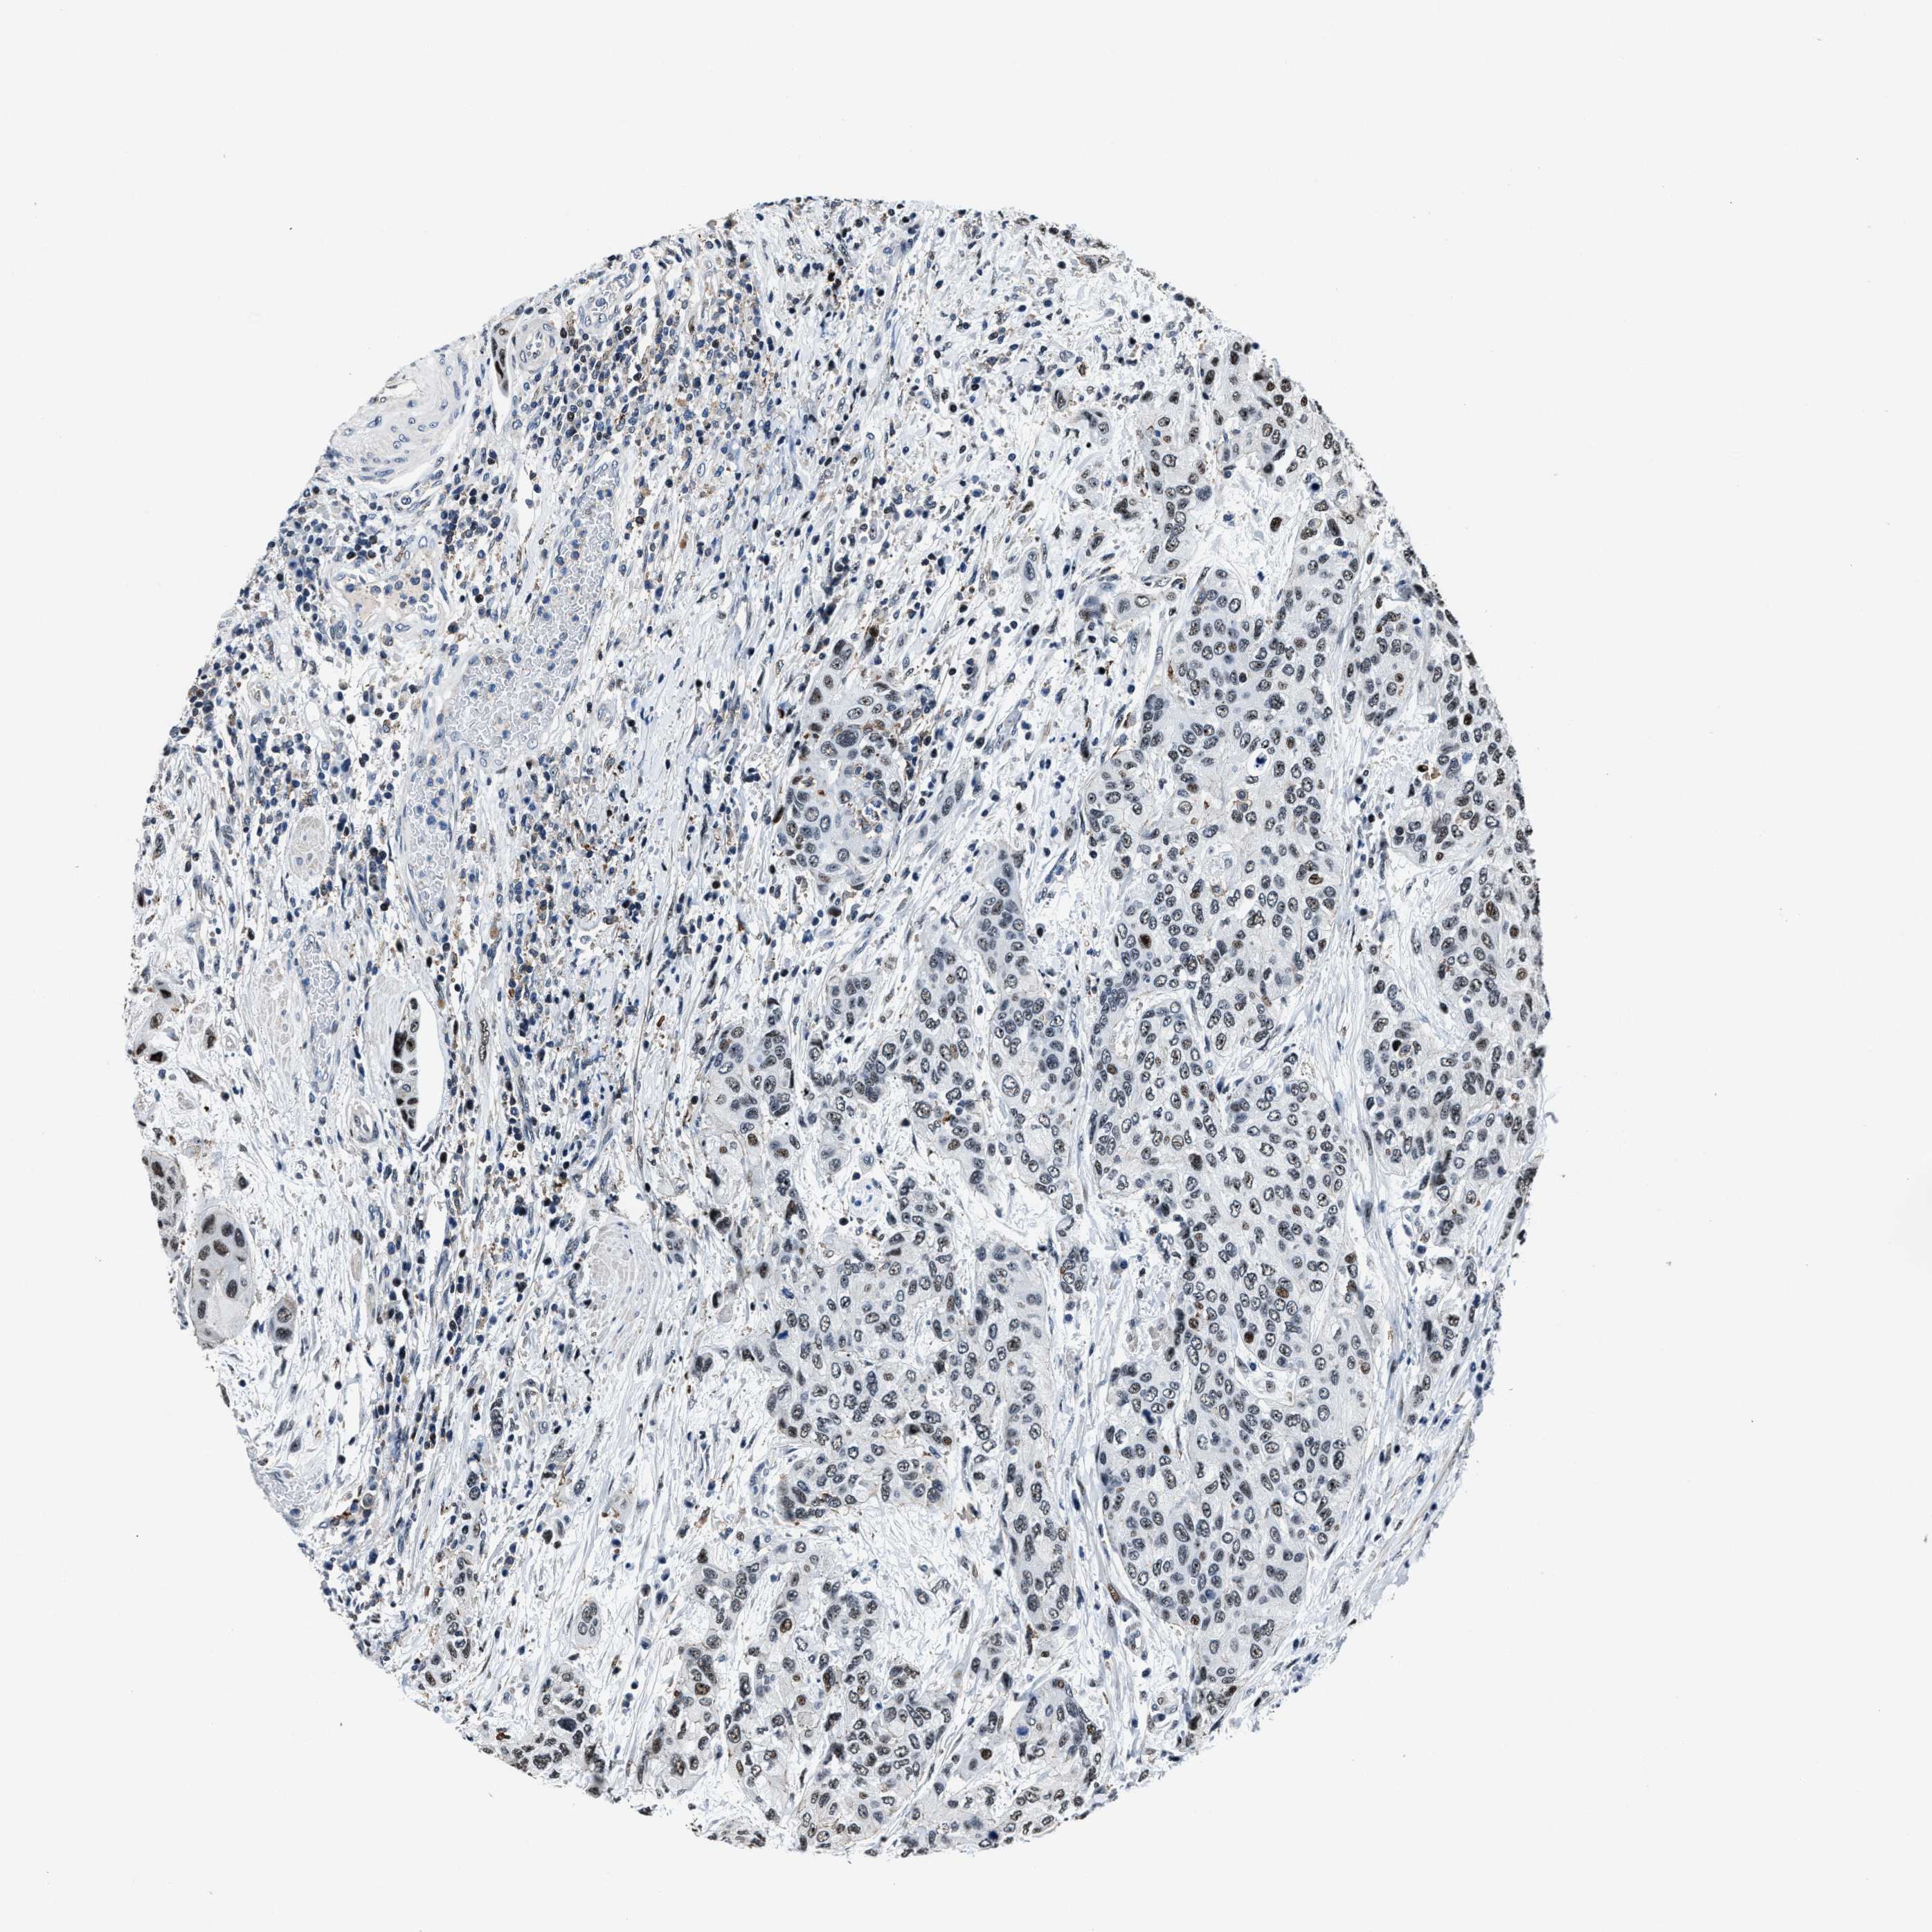

UROTHELIAL CANCER - Protein expressioni

A mouse-over function shows sample information and annotation data. Click on an image to view it in a full screen mode. Samples can be filtered based on level of antibody staining by selecting one or several of the following categories: high, medium, low and not detected. The assay and annotation is described here.

Note that samples used for immunohistochemistry by the Human Protein Atlas do not correspond to samples in the TCGA dataset.

Antibody stainingi

Antibody staining in the annotated cell types in the current human tissue is reported as not detected, low, medium, or high, based on conventional immunohistochemistry profiling in selected tissues. This score is based on the combination of the staining intensity and fraction of stained cells.

Each image is clickable and will lead to virtual microscopy that enables deeper exploration of all samples and also displays staining intensity scores, fraction scores and subcellular localization as well as patient and tissue information for each sample.

Antibody HPA020131

Staining

High

Medium

Low

Not detected

Intensity

Strong

Moderate

Weak

Negative

Quantity

>75%

75%-25%

<25%

None

Location

Urothelial carcinoma, Low grade

Urothelial carcinoma, High grade